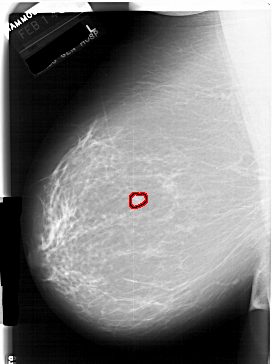

FILE: A_1940_1.LEFT_MLO.OVERLAY

TOTAL_ABNORMALITIES 1

ABNORMALITY 1

LESION_TYPE MASS SHAPE LOBULATED MARGINS CIRCUMSCRIBED

ASSESSMENT 3

SUBTLETY 4

PATHOLOGY BENIGN

TOTAL_OUTLINES 1

BOUNDARY